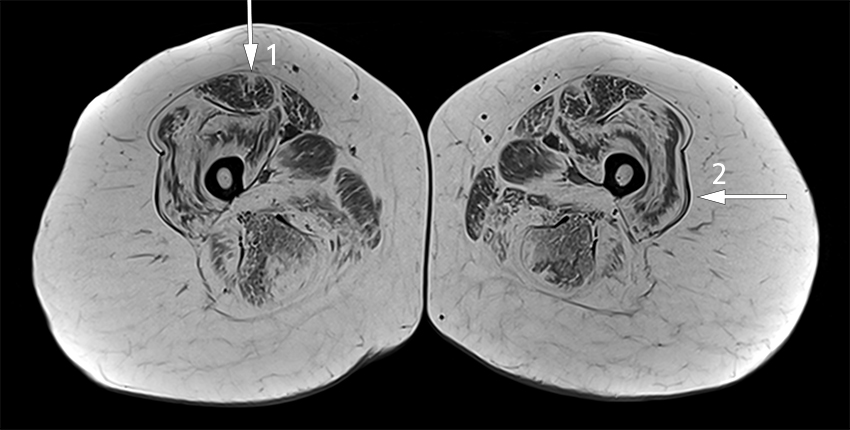

Based on a clinical examination consistent with myopathy, positive genetic testing and previously demonstrated fatty infiltration on MRI, there was no indication for electromyography. With the woman's consent, her clinical presentation was discussed anonymously in a national video conference with colleagues across Norway working with rare muscular diseases. It was recommended that MRI scanning of all muscles be performed, which revealed a characteristic pattern of fatty infiltration, predominantly in the proximal muscles of the upper and lower extremities (Figure 1).

MRI scanning is being increasingly used to investigate diseases affecting the muscles, primarily to select a suitable biopsy site, but also as a diagnostic tool to identify the extent and pattern of muscle oedema and fatty infiltration. Collagen VI-related myopathies such as Bethlem myopathy have a distinct, but not pathognomonic pattern with central fatty infiltration in the rectus femoris muscle and peripheral fatty infiltration in the vastus lateralis muscle with relative sparing of the central region, resulting in a 'sandwich sign' (12–14).